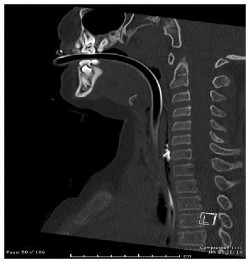

Coupe sagittale (symétrique) de la colonne cervicale montrant des éclats de vitres dans l’oesophage masqués par le tube endotrachéal.